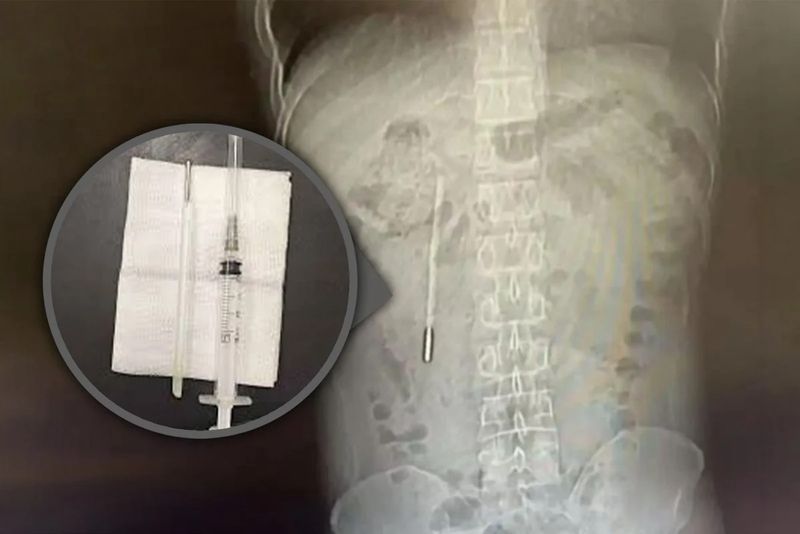

Un bărbat din China, în vârstă de 32 de ani, a mers la spital cu dureri puternice de stomac, dar medicii au descoperit ceva incredibil în corpul său: un termometru înghițit pe vremea când era copil.

Chinezul a ajuns la spital din cauza durerilor de stomac, dar medicii au fost uimiți să descopere că un termometru cu mercur pe care îl înghițise în urmă cu peste 20 de ani se afla încă în interiorul său.

O scanare rapidă a relevat un obiect străin în duoden, despre care medicii suspectau că ar fi un termometru cu mercur.

Deoarece vârful termometrului apăsa direct pe peretele intestinal, acesta prezenta un risc ridicat de perforație și hemoragie internă severă.

Chirurgii au efectuat o operație de urgență pentru a îndepărta obiectul care i-a provocat probleme. Din fericire, dispozitivul extras a rămas intact, fără pierderea mercurului din interior.

Operația a fost una delicată, deoarece termometrul fusese reținut o perioadă lungă de timp și se afla aproape de canalele biliare ale lui Wang, prezentând un risc semnificativ de deteriorare a peretelui intestinal.